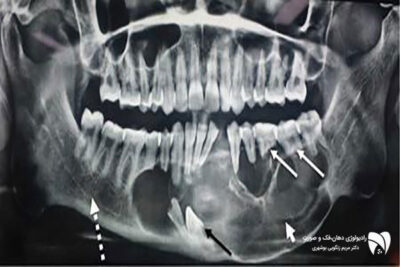

تشخیص ضایعات فکی به صورت دقیق با روش‌های تصویربرداری دهان و تصویربرداری دقیق مفصل فکی، دقت و سرعت را در شناسایی مشکلات فک افزایش می‌دهد.

چگونه ضایعات فکی را با دقت تشخیص دهیم

تشخیص ضایعات فکی موضوعی است که در این مطلب به اهمیت آن پرداخته می‌شود و به این موضوع می‌پر...

ارزیابی دقیق دندان‌ها و فک‌ها با رادیوگرافی فک و تصویربرداری دندان، شامل رادیوگرافی فک و سی‌تی‌اسکن دندان. راهنمای انتخاب روش مناسب تصویربرداری.

ارزیابی کلی وضعیت دندان‌ها و فک‌ها با استفاده از تصویربرداری پیشرفته

تصویربرداری دندان یکی از ابزارهای کلیدی در تشخیص و ارزیابی مشکلات دهان و فک است. در این مط...